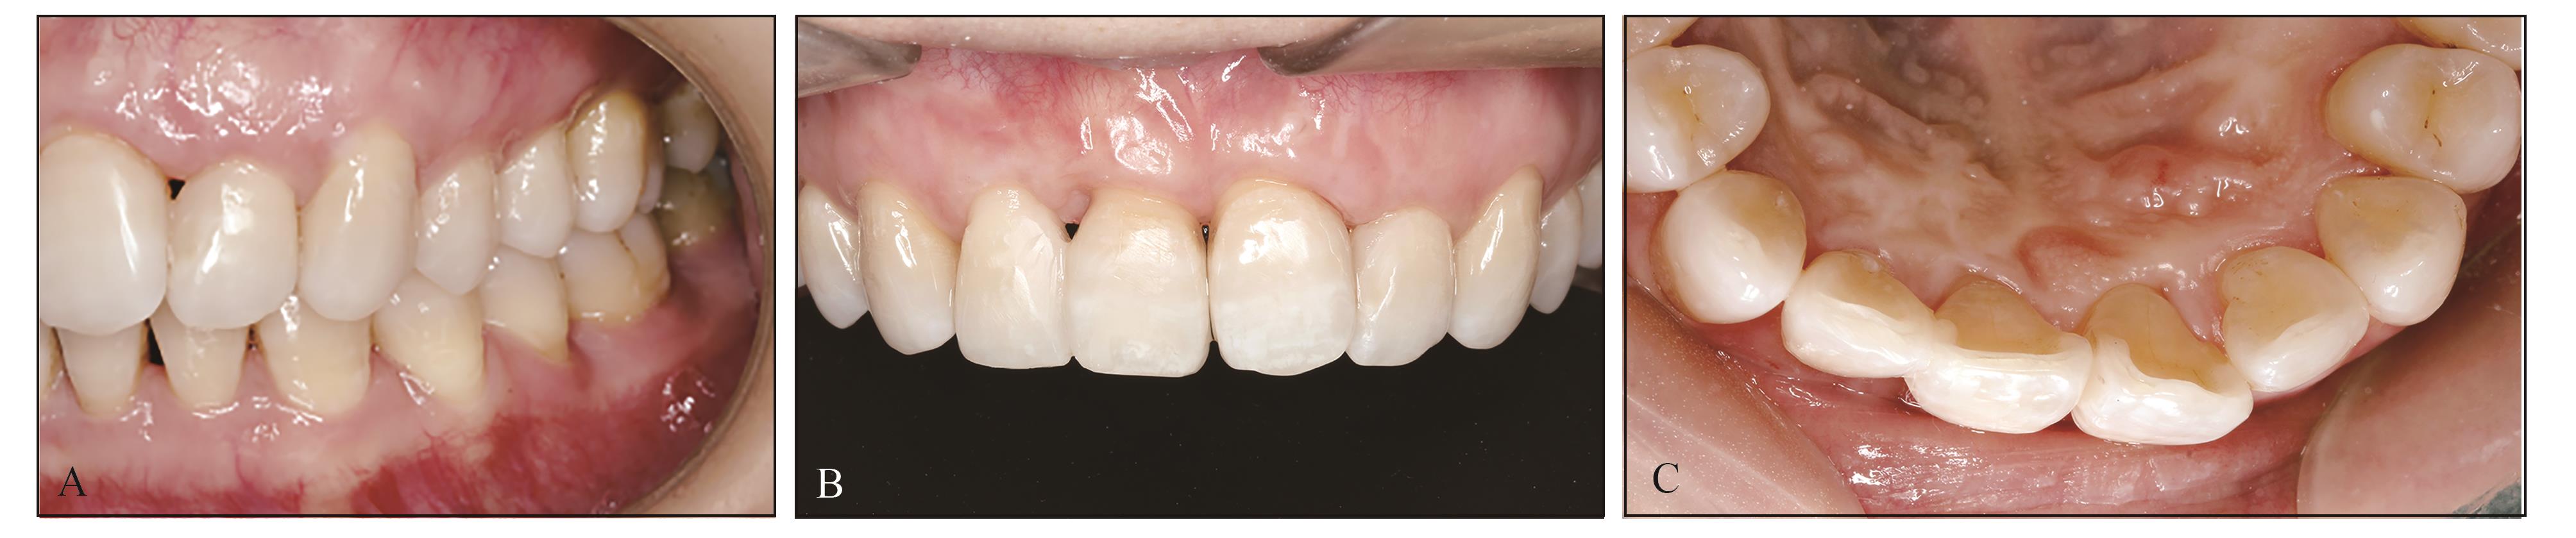

图 7

术后15个月口内照A:唇侧左侧面照;B:唇侧正面照;C:腭侧照。"